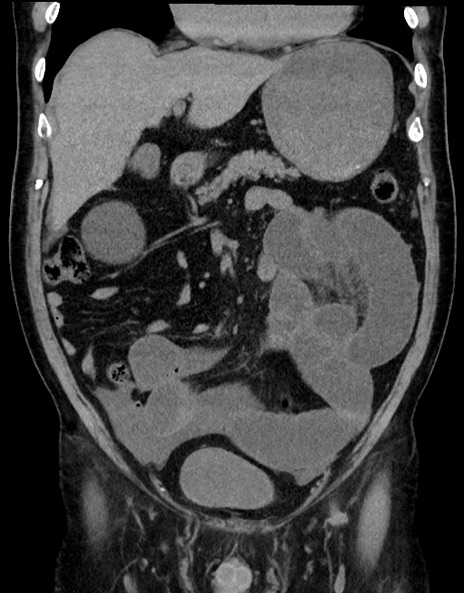

症例15(冠状断像)

【症例】70歳代男性

【主訴】腹痛

【現病歴】今朝から腹痛あり。全体的に痛い。特に左上の方。排ガスが今日はない。冷や汗が出る。

【既往歴】直腸癌術後

【身体所見】左側腹部〜上腹部に圧痛あり。腹膜刺激症状明らかなではない。軽度反跳痛。左下腹部に術後瘢痕あり。

【データ】WBC 7700、CRP 0.02

横断像